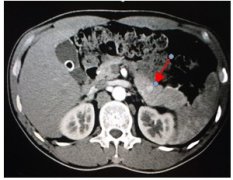

胰島素瘤指因胰島細(xì)胞瘤或細(xì)胞增生造成胰島素分泌過(guò)多,進(jìn)而引起 低血糖癥 ;其胰島素分泌不受低血糖抑制。低血糖癥是一組由多種病因引起的以血糖濃度低為特點(diǎn)的綜合征,一般以靜脈血...

• 胰島素瘤

胰島素瘤指因胰島細(xì)胞瘤或細(xì)胞增生造成胰島素分泌過(guò)多,進(jìn)而...